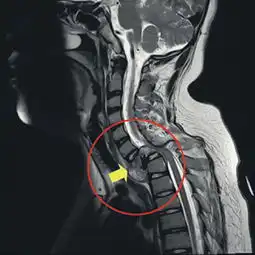

脊椎被吃掉一截台湾男童患罕见病瘫痪不治